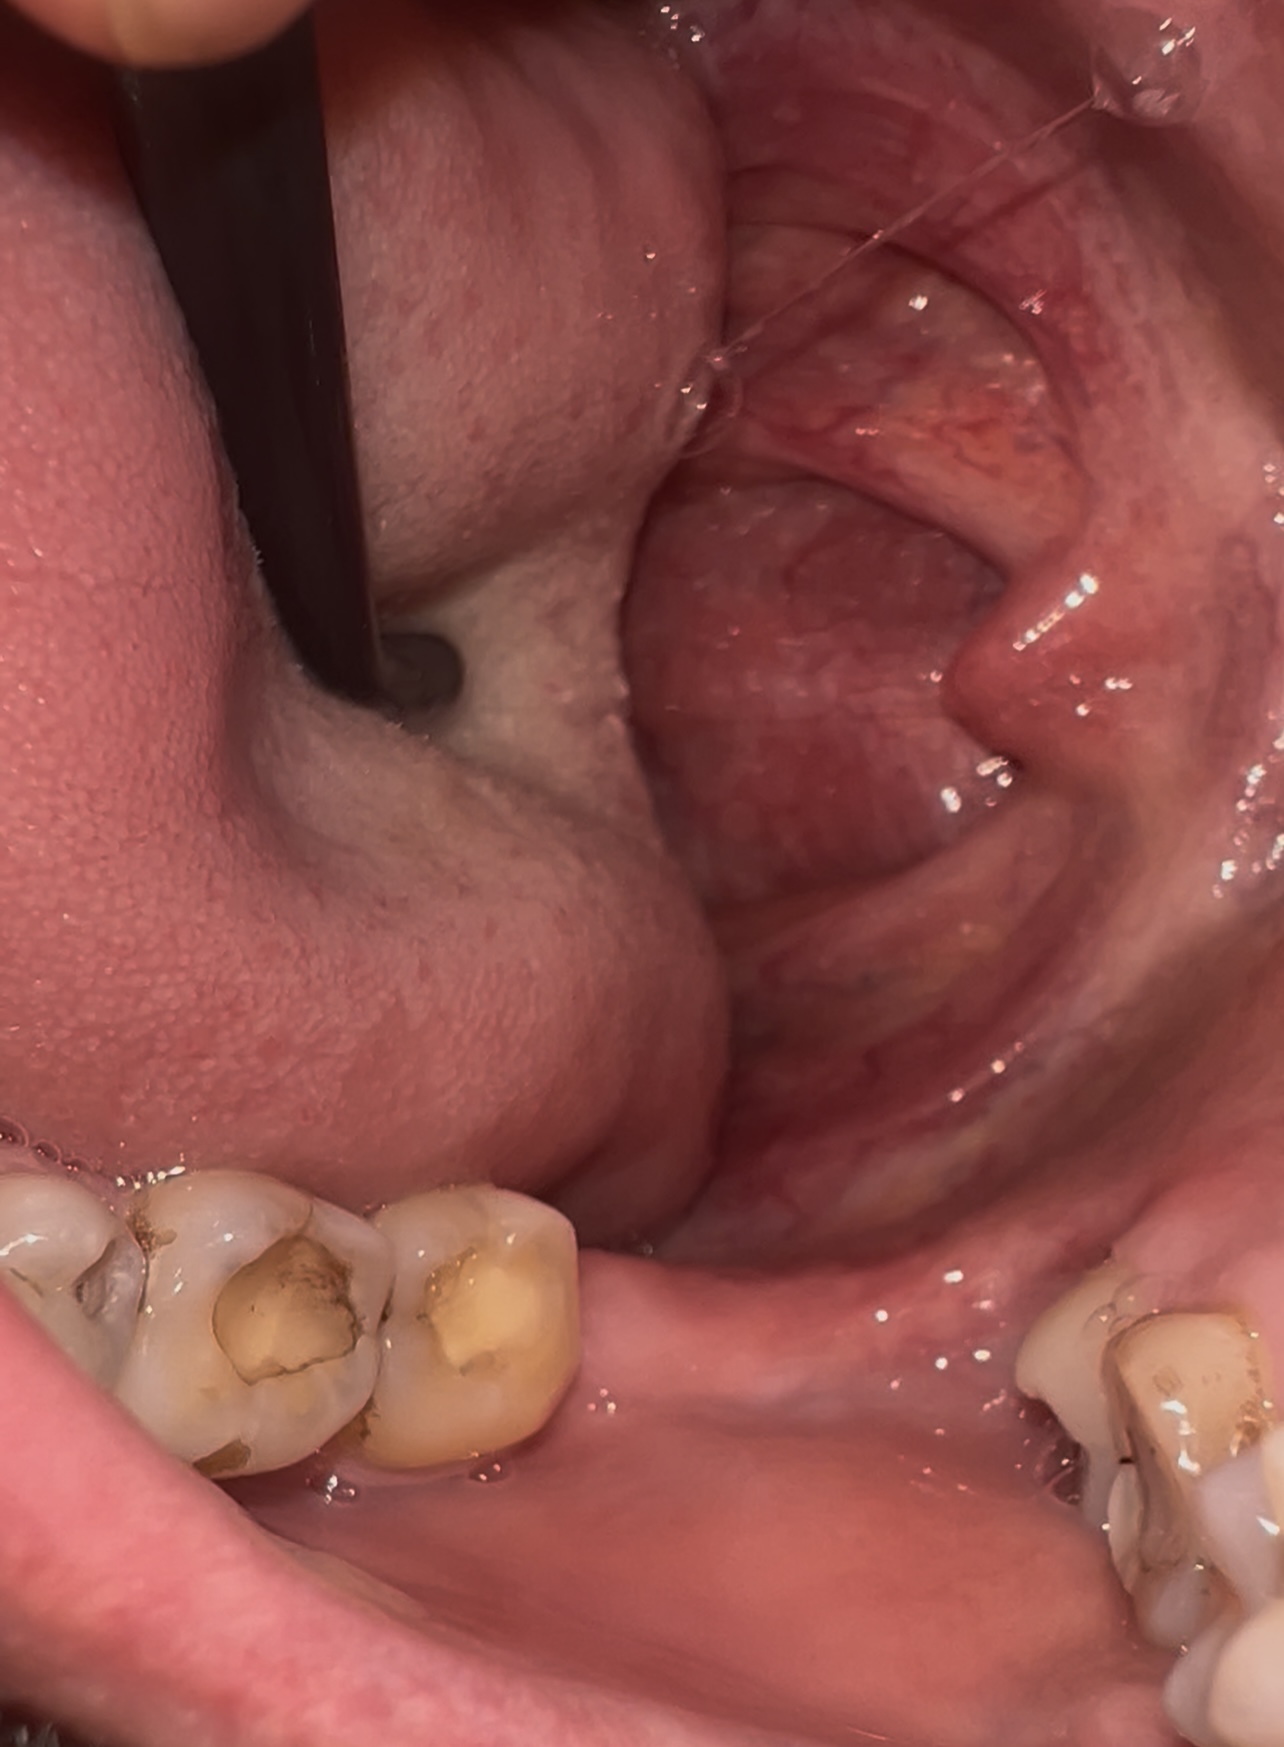

Аноним 20/09/25 Суб 01:48:37 1640597 146

IMG202509200045[...].jpg 4062Кб, 3468x4624

3468x4624

Всем сап, растёт эта хреновина вбок из десны к щеке, только удалять?

Насколько плохо, что не озаботился этим раньше? Стало больно глотать и плевать, отдаёт болью в десну, будто потянул её